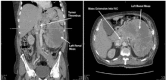

A 52-year-old man without known medical history presented with painful, progressive, bilateral lower extremity edema over a two-week period. An abdominal exam noted a firm left upper quadrant mass. Emergency department (ED) point-of-care ultrasound (POCUS) revealed a hyperechoic, heterogeneous structure in the inferior vena cava that was determined to represent a tumor thrombus extending from a primary renal cell carcinoma. This case demonstrates how POCUS was valuable in rapidly diagnosing this rare cause of lower extremity edema and its usefulness in directing the initial ED management of this patient.